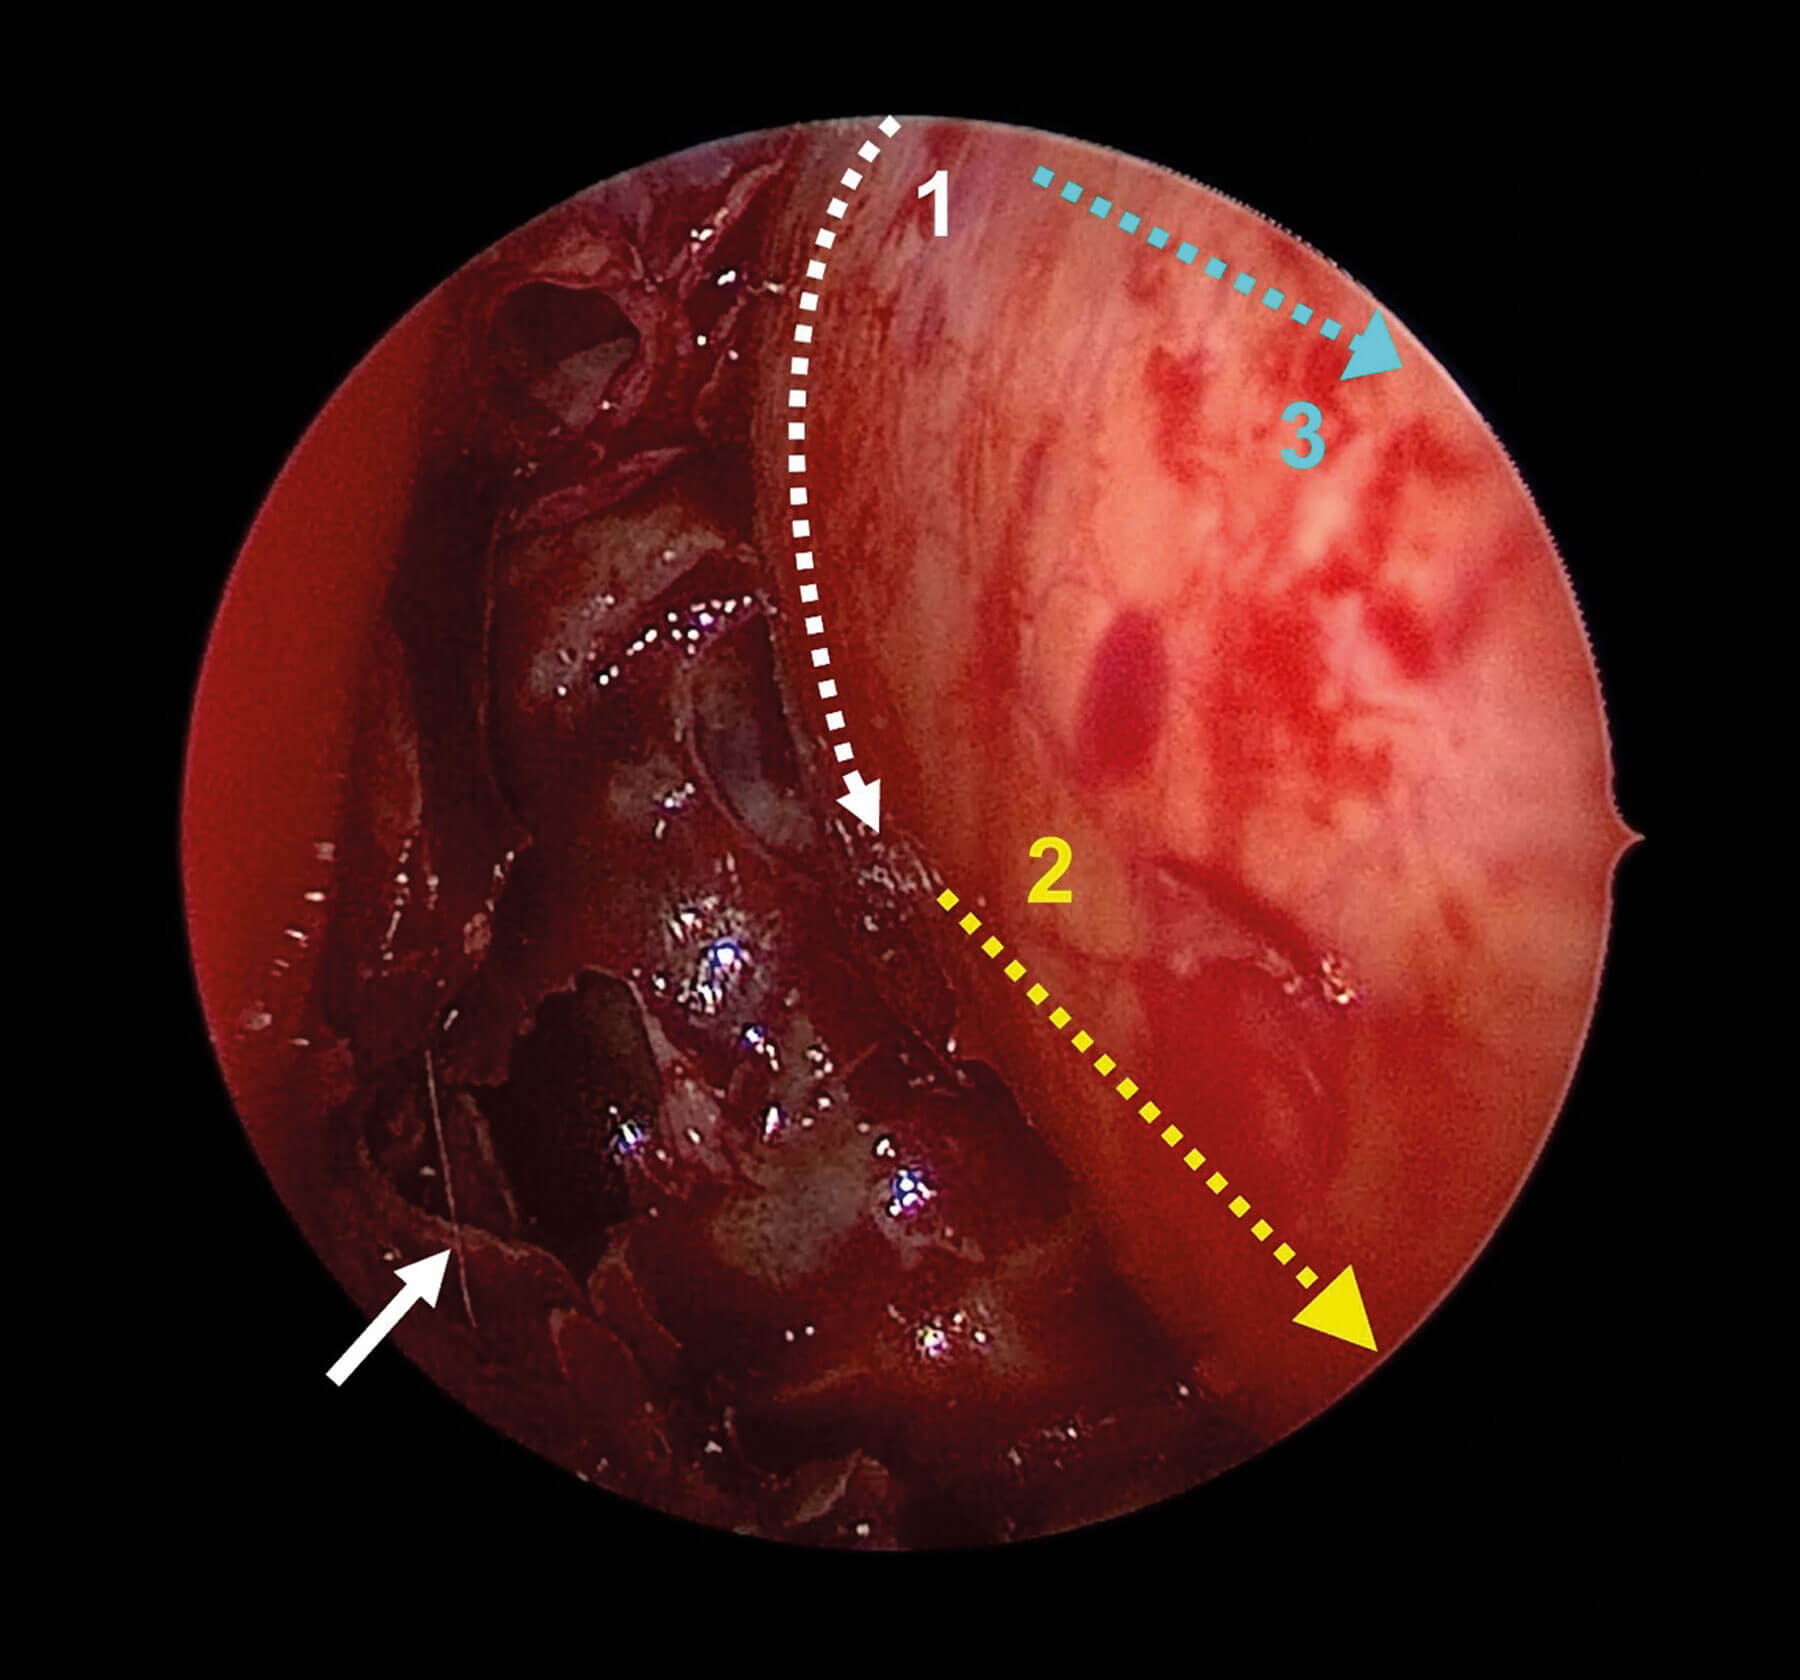

Temporoparietal fascia flap for blind sac closure

Chronic ear disease can be challenging to manage and difficult for patients to live with. In this article, the authors describe their technique for otomastoid obliteration and blind sac closure of the external canal allowing for a more tolerable situation...